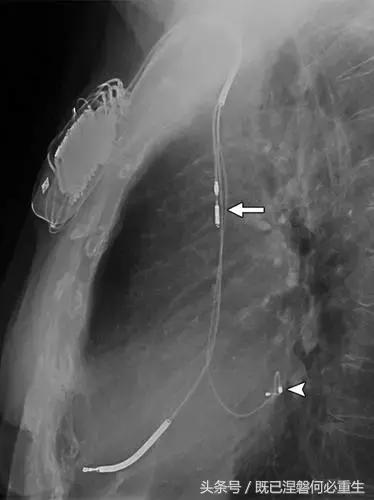

用于将导线的近端部分固定到胸壁的导线固定件可以模拟损伤。扎带是通常位于锁骨和发生器之间并且可以压接引线的套囊(图8A和8B)。熟悉这种外观和通常的射线透射束缚的位置可以防止错误报告磨损的线索。

图。 8A在两个不同患者中电极断裂的电极结合物的实例。

图。 8B在两个不同患者中电极断裂的电极结合物的实例。